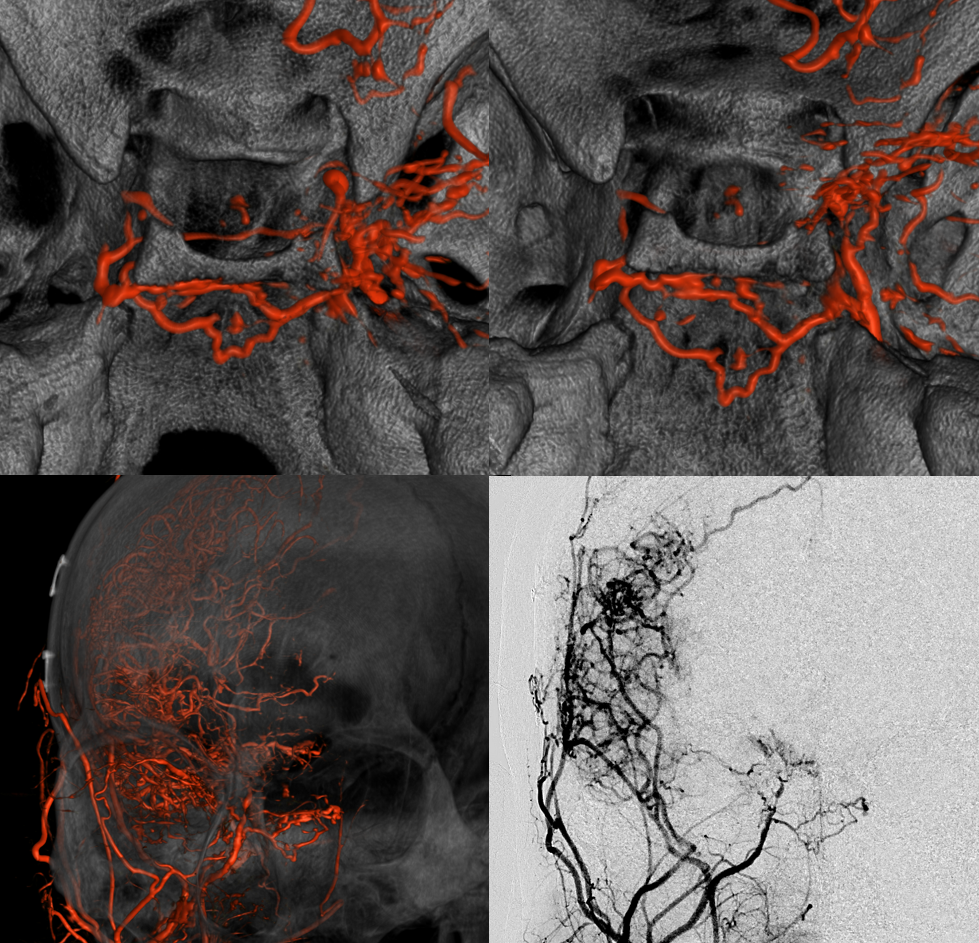

Below is the same case, imaged in 4 different ways. See for yourself. Top left — 2D-DSA. Top right — low resolution Cone Beam CT (3D-DSA), subtracted. Bottom left — low resolution Cone Beam CT (3D-DSA), UNsubtracted. Bottom right — high resolution Cone Beam CT (DYNA), unsubtracted.

Circa 2010 3D-DSA of the same